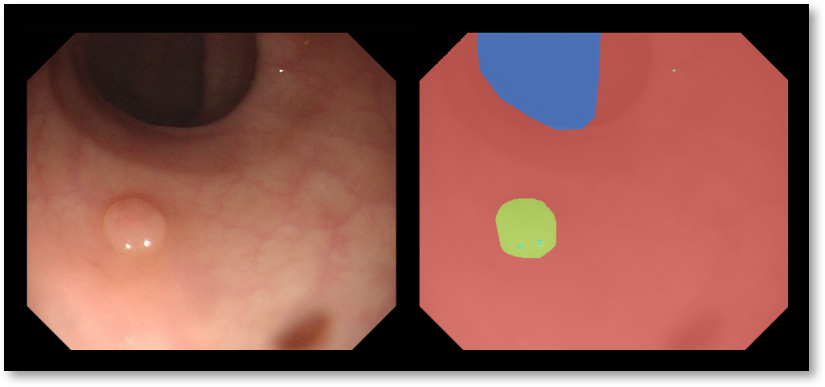

Refer to caption

Figure 1: (a) Colonoscopy image and corresponding labeling: blue for lumen, red for background (mucosa wall), and green for polyp, (b) Proposed pipeline of a decision support system for colonoscopy.